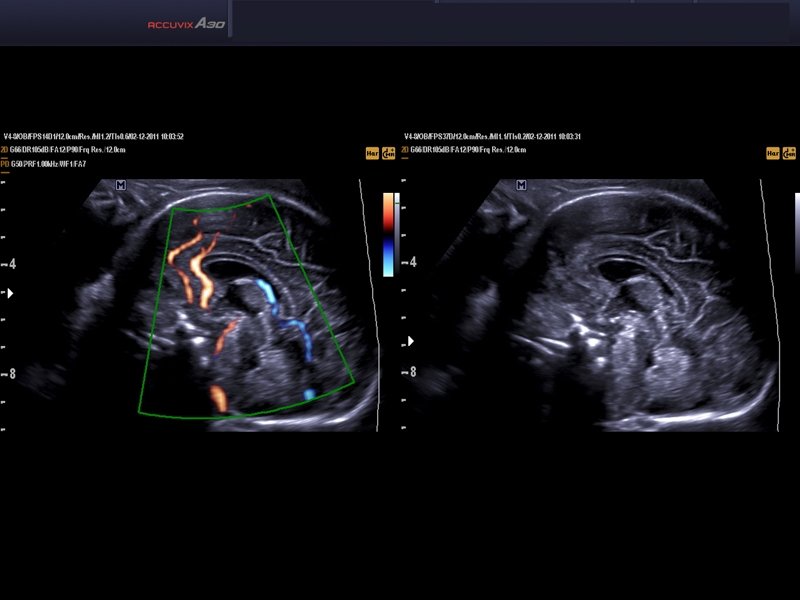

Fetal brain, DPDI & DMR (echogramm №566)

[RU] Ultrasound image №566: Fetal brain in DPDI mode, THI (tissue harmonic) and DMR.

Echogramm was received by ultrasound scanner Accuvix-A30 (out of production).